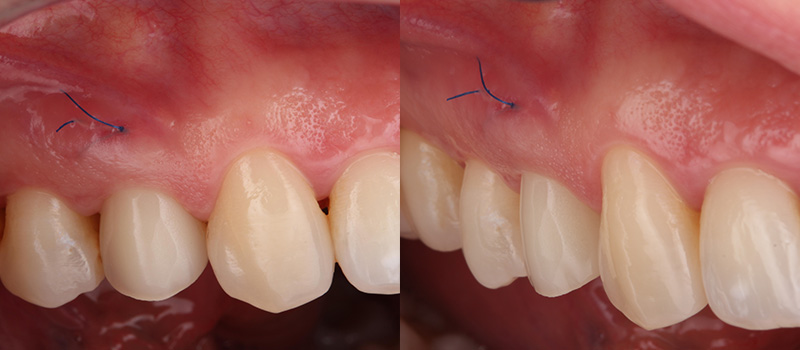

Fig. 05 : situation clinique à J10 (avant la dépose de la suture en 6.0 monofilament) vue latérale et vue vestibulaire.